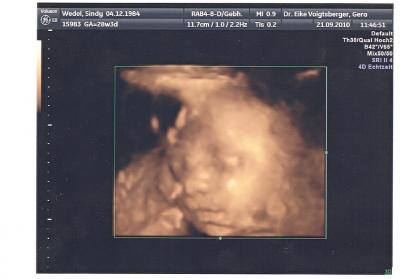

Hallo ihr Lieben! Nach langem drücken auf dem Bauch, konnte der Doc doch noch so halbwegs ein schönes Bild von dem kleinen Mann machen. Leider hatte sich die Nabelschnur noch etwas übers Gesicht gelegt und somit müssen wir uns mit dem ergebnis so zufrieden geben. Aber besser wie kein Bild! So morgen hab ich nach 9 Wochen endlich wieder VU mit US! Bin ja schon ziemlich gespannt auf die aktuellen Maße des kleinen Mannes! Ich freu mich voll!!!

Bild zu Erfolfreich gewesen beim 3 D! - Forum für Dezember - Mamis